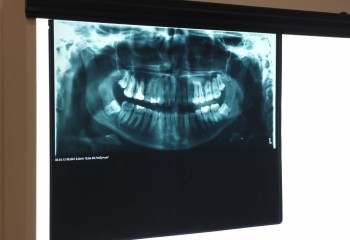

Poniższa galeria zawiera zdjęcia przedstawiające sprzęt znajdujący się w szkolnej pracowni RTG: aparat RTG, sprzęt komputerowy, zdjęcia rentgenowskie.